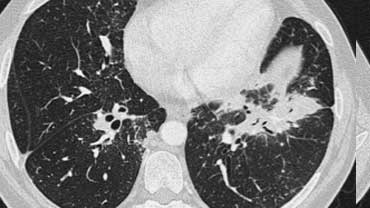

Tiếp tục với hình ảnh HRCT.

Hãy cuộn qua các hình ảnh bên trái.

Có nhiều vùng đông đặc.

Các dấu hiệu kèm theo bao gồm hạch to rốn phổi và trung thất.

Chẩn đoán phân biệt trên hình ảnh CT về cơ bản giống như trên X-quang ngực.

Kết quả mô bệnh học xác nhận sarcoidosis phế nang.

Chỉ có một gợi ý duy nhất cho chẩn đoán, đó là sự hiện diện của các nốt nhỏ có thể nhận thấy ở hình 3, nhưng rất khó quan sát.

Trường hợp này minh họa rõ ràng rằng sarcoidosis thực sự là “kẻ bắt chước vĩ đại”.

Do đó, sarcoidosis cần được đưa vào danh sách chẩn đoán phân biệt của chúng ta!